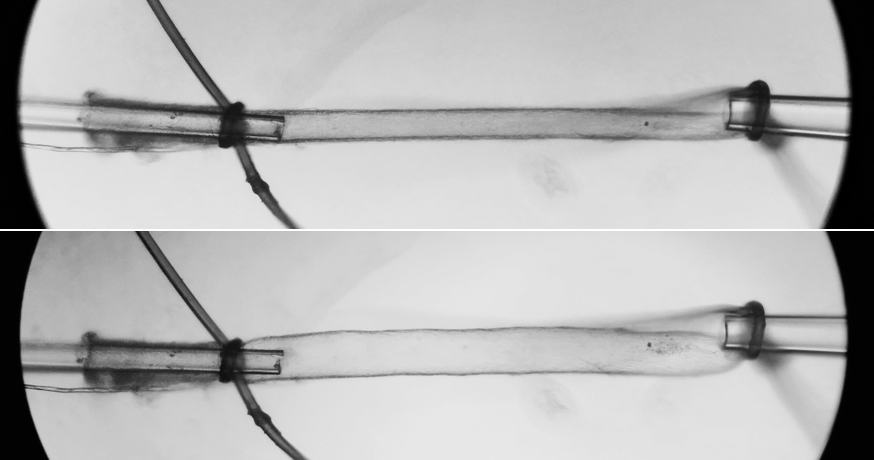

In this picture, you can see a vessel after I have placed it on the glass tubes and tied string around it to keep it in place. The top picture shows the vessel before I have blown it up. The bottom picture shows the exact same vessel after I blow it up. You can see that it inflates.